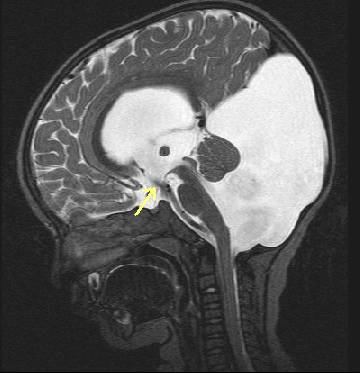

Tanı anne karnında doğum öncesinde ültrason veya MR ile konabilir (Resim 3). Tüm hastalarda mümkün olduğunda MR çekilip diğer bozukluklar da araştırılmalıdır. Tedavi hidrosefali gelişirse söz konusudur. Şant ameliyatı ve endoskopik ameliyat uygulanmaktadır (Resim 4).

Resim 4: Endoskopik üçüncü ventrikülostomi uygulanmış bir hastanın MR’ında 3. karıncık tabanında açılmış olan pencereden BOS akımı (ok) görülmektedir.